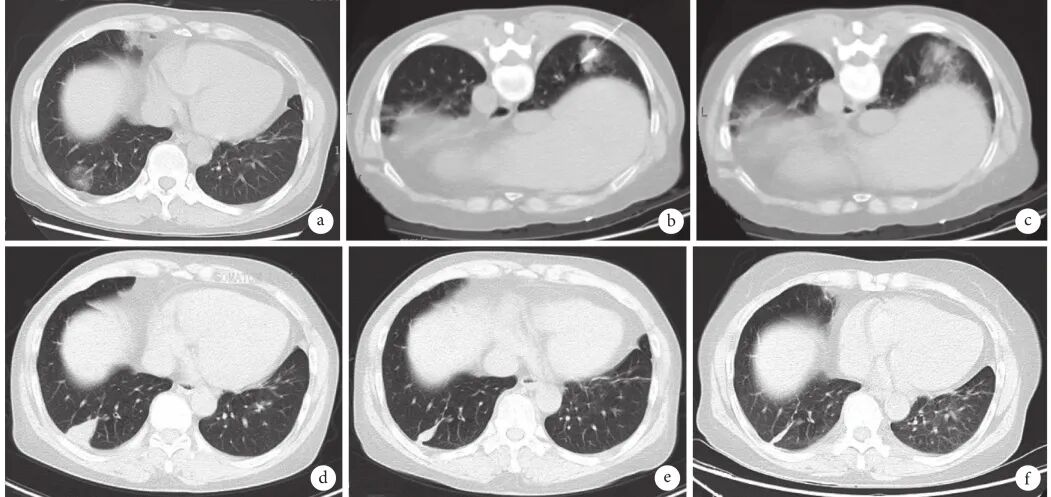

肺磨玻璃结节(ground-glass nodule,GGN)是体检或偶发早期肺癌的主要表现形式,常见于年轻、女性和不吸烟人群,正确的随访与处理策略可在降低肺癌死亡率的同时避免过度治疗。持续存在的GGN大多数为腺癌或前驱腺体病变,但呈惰性生长或长期不生长,有条件的随访是十分安全的。GGN必须采取个体化诊治策略,在充分考虑浸润程度、动态变化、治疗疗效与并发症、患者身体状况及心态等因素后做出治疗决策。不同于其它类型肺癌的尽早治疗策略,GGN型肺癌治疗时间窗很宽,必须在充分考虑治疗利弊后确定治疗时机。 外科手术是主要根治手段,对表现为GGN的前驱腺体病变目前普遍采取亚肺叶切除及不清扫淋巴结的术式。鉴于绝大多数GGN型肺癌属于无转移的局部病变,对不宜或不愿外科手术者可考虑采用介入根治。一般采用经皮微波、射频及氩氦刀等消融技术进行介入根治,具有创伤小、对肺组织损伤轻、可多次操作及可同步活检等优点,现有的研究结果已证实了消融治疗的可行性。超声与导航引导下经支气管消融治疗肺结节的疗效已初步得到了证实,是介入根治GGN的新途径。 未来在GGN的治疗上,消融治疗有望与外科手术同等重要,根据病灶特点、部位及患者情况等来选择治疗方法,以求患者利益最大化。近几年来,消融治疗 GGN 的探索逐渐增多。本文将在进一步认识 GGN 的基础上,探索 GGN 的诊治策略,并从呼吸介入角度,介绍消融治疗在 GGN 中的应用。 关键词:磨玻璃结节;诊治策略;经皮消融;根治 【正 文】 肺部磨玻璃结节(ground-glass nodule,GGN)指高分辨率CT表现为肺内边界清楚或不清楚的直径(或最大径) ≤30 mm的圆形或类圆形密度增高阴影,但病变密度不足以掩盖其中走行的血管、支气管、小叶间隔等结构,可为单发或多发,不伴有肺不张、肺门及纵隔淋巴结肿大和胸腔积液。 随着影像技术的发展、肺癌筛查的普及,GGN的检出率明显上升,因其与肺腺癌密切相关而备受关注。近年来多个国家、地区开展了肺癌筛查研究并提示,肺癌高风险人群中GGN的发病率为2.0%~3.3%。国内有报道在普通人群筛查发现的肺癌中,84.8%~95.5% 的患者在影像学上表现为GGN。与传统观念中的肺癌好发人群不同,大量研究数据显示恶性GGN好发于年轻、非吸烟、女性。 目前GGN在筛查、随访、治疗策略等方面缺乏共识,手术仍是拟诊GGN型肺癌根本的治疗策略,尽管最佳术式还存在争议。随着介入消融技术的发展,其应用范围也在不断拓宽。近几年来,消融治疗GGN的探索逐渐增多。本文将从GGN认识上的进展、诊治策略及经皮消融技术根治GGN的现状与探索等方面展开。 GGN根据是否存在实性成分可分为:纯磨玻璃结节(pure GGN,pGGN)和混合磨玻璃结节(mixed GGN,mGGN),前者又被称为无实性结节,后者又被称为部分实性结节(图1)。GGN的病理基础是肺泡间隔增厚,或部分肺泡腔充满液体、细胞或组织碎片,因此GGN并非某病的特异表现,它既可见于浸润性肺腺癌、腺体前驱病变,又可见于局灶性间质纤维化、肺泡出血、炎症或细支气管上皮增生、细支气管周上皮化生等。持续存在的GGN是指结节至少持续存在3个月以上且复查时未变小或消失。应特别重视持续存在的GGN,因其多为恶性或有向恶性发展的潜能。Kim等报道有超过80%持续存在的GGN最终被诊断为腺癌或前驱腺体病变。Lim等的研究也发现,最大径≥10 mm持续存在的pGGN手术病理100%为腺癌或前驱腺体病变。 GGN型肺癌均为腺癌,多数学者认为是经有序的多阶段发展而来的。从影像上由pGGN发展为mGGN或实性结节。在病理学上,通常是由非典型腺瘤样增生(atypical adenomatous hyperplasia,AAH)到原位腺癌(adenocarcinoma in situ,AIS),再进一步发展为微浸润腺癌(minimally invasive adenocarcinoma,MIA)、浸润性腺癌(invasive adenocarcinoma,IAC)。 GGN是一种非特异性的影像学表现,但其影像特点对于判断病理性质帮助很大,多数GGN的影像与病理存在相关性。纯磨玻璃影被认为是AAH或AIS的表现,当pGGN<5 mm时多为AAH;介于5~30 mm,AIS的可能性最大。 但值得注意的是,即便是pGGN,少数可能是MIA,极少数甚至已是IAC,其中大部分为贴壁生长型,但也有少数呈非贴壁生长型。而对于mGGN,当实性成分直径<5 mm以MIA多见,≥5 mm则提示IAC的可能性较大。GGN病灶越大,实性成分越多,其恶性可能性越大,侵袭性越强。此外,结节的形态,边缘(毛刺征、分叶征、血管集束征)及内部结构特征(CT值、空泡征、支气管充气征等)也是鉴别良恶性、侵袭性的重要影像征象。 现有的研究数据表明40%~50%的GGN在随访3~4个月时消失,这些属于暂时性GGN,考虑为良性病变。持续存在的GGN虽然多为腺癌或前驱腺体病变,但长期随访多无变化,仅少数出现生长。Chang 等报道122个pGGN随访近5年,90.2%未见生长。日本国立癌症研究中心牵头的一项多中心前瞻性研究发现,在4.3年的平均随访期内,1 046例pGGN中仅6.6%发展为mGGN。与pGGN相比,mGGN在随访中出现生长的比率较高。Sawada等的研究发现24.2%的mGGN在5年随访期内生长,远高于pGGN的12.8%;而且实性成分占比(consolidation/tumour ratio,CTR) 越高,生长的可能性越大,CTR 0.1~0.25、0.26~0.5、>0.5的mGGN随访5年的生长率分别为14.2%、28.6%、30.8%。GGN即使生长也呈惰性缓慢生长,倍增时间很长。根据研究报道mGGN的倍增时间是457~568 d,pGGN更是长达469~845 d。有研究数据表明,GGN的生长绝大多数发生在3~5年内。有一项研究报道CTR<0.5的108个GGN,平均随访4.2年,26.9%在随访期内增大,且均在随访3年内出现。Lee等报道了351个GGN随访10年的研究数据,发现后5年的GGN生长率不及前5年的1/3。对GGN生长规律的了解,有助于我们做出正确的处理策略,避免过度诊治。 如前所述,持续存在的GGN多数为腺癌或前驱腺体病变,根据影像特点是无法排除恶性病变的。因此,高分辨率CT发现GGN后如果3个月随访无缩小或消失就需要进行长期随访,直至可排除恶性。GGN生长缓慢或长期无改变,故随访期限一般至少5年。随访时间间隔应根据恶性风险及可能的浸润程度、患者的具体情况而定。 目前在国内外有许多相关的指南、共识,但由于各指南、共识制定者的专业背景、地域以及针对人群的不同,推荐的GGN随访策略差异较大。其中几个主要指南、共识的随访策略归纳见表1。指南及共识的策略差异导致了临床医生的困扰,但在临床工作中这些指南、共识只能提供参考,在对GGN的具体处理上应针对不同患者、病灶制定个体化的随访策略。 表1 国内外主要指南、共识对磨玻璃结节随访及处理的建议总结 我们结合长期的临床经验,提出以下几点供参考: GGN初次发现后均应3个月随访,大多数良性GGN会有缩小或消失; 首次随访无变化者应根据影像特征评估恶性风险及可能的病理类型,可疑AAH者可年度或2年后随访,可疑AIS者可6~12个月后随访,可疑MIA者 3~6个月后随访,可疑IAC者 3个月后随访或考虑活检、治疗; 后续随访时间间隔根据前一次随访评估的病理类型确定,在动态随访中如出现结节增大、实性成分增加或新出现恶性征象应缩短随访间隔或进行活检、治疗,如病灶持续稳定,可适当延长随访间隔时间; 必须结合患者身体状况及心态等因素来确定GGN的随访策略。对于预计生存期有限的高龄、合并严重慢性疾病患者,随访不宜过于积极,甚至可长期不随访;对于心态十分焦虑的患者,随访应相对积极。 GGN密度较低且存在正常的肺内血管,与实性结节相比非手术活检确诊率相对较低、出血风险较大,同时对恶性的浸润程度判断也欠准确。然而,非手术活检仍是GGN除外科手术以外唯一的确诊手段,具有明确病变性质以便对因治疗、避免外科误切、缓解患者心理压力等作用。因此,严格筛选非手术活检的适应人群及充分掌握活检技术也是GGN诊治策略的重要一环。 GGN非手术活检的主要适应证包括:有典型恶性特征但不愿或不宜外科手术、疑诊为可经内科治愈但病因不明的良性疾病、同时存在类似的多发结节且不能排除恶性;且均必须通过评估确认非手术活检可取到合格标本。活检途径分为经皮及经支气管两种,前者宜用于无支气管相通、活检部位无明显血管的病灶,后者则主要用于与支气管管腔相通的结节病灶。经皮穿刺活检是肺结节诊断的传统有效技术,报道的GGN诊断率约64.6%~93%。对≤1 cm的GGN确诊率差别更大,48.5%~87%不等。近来,经引导鞘管超声支气管镜(endobronchial ultRASonography with a guide sheath,EBUS-GS)及导航技术的应用,大大提高了GGN经支气管活检的确诊率及安全性,其阳性率达到57%~69%,病灶越大阳性率越高,而且高分辨率CT可见支气管与病灶中间相通者确诊率更高。冷冻活检能够取到较大的标本,有望明显提高诊断率。有研究[49]报道EBUS-GS联合超细探头冷冻肺活检诊断率可达到82.61%,且诊断率与病灶大小、CTR、是否采用导航或X线透视等因素无关,值得进一步探索。 除非高度怀疑真菌感染或浸润性肺癌,一般需在随访3个月以上才考虑活检,以避免不必要的活检。 GGN病灶及其周围存在正常肺部血管,经皮穿刺活检进针及活检切割时必须尽量回避较大血管,防止大出血。 pGGN经皮穿刺活检阳性率较低且出血风险大,必须慎用。 如病灶部位血管丰富,于微波或射频热消融中或消融后进行经皮穿刺活检可减少出血量、提高安全性,且不影响活检的病理检查结果。 为提高诊断率及减少并发症,经支气管镜活检应该在超声探头可探及病灶的前提下进行,冷冻肺活检最好在X线实时透视下采用细探头取材。 外科手术切除是拟诊恶性GGN的主要治疗方法。《上海市肺科医院磨玻璃结节早期肺腺癌的诊疗共识(第一版)》中对可疑AIS、MIA及IAC的GGN的手术指征做了较为详细的说明,但病理类型仅通过影像特征分析得出,存在不准确的可能性。 目前相对比较一致的观点是当多学科会诊后高度怀疑IAC病变时,应手术干预。对于影像特征怀疑为AIS或MIA时,需要根据病变部位、随访时间长短、发展为浸润病变的概率等因素综合考虑。GGN型肺癌是一种惰性的肿瘤,有条件随访十分安全,治疗窗口期很长。因此,对前驱腺体病变不应过早积极手术干预,以避免过度治疗。另外,是否考虑手术治疗必须结合病灶部位、结节数量、患者的预计生存期及心态等,对于非优势部位、双侧多发、高龄或有严重基础疾病者手术宜消极,反之则可积极考虑手术治疗,当患者对GGN十分焦虑时手术指征也可适当放宽。 随着临床研究的深入,临床医生对GGN的切除范围有了更准确的认识。基于1995年的一项随机对照研究(RCT),肺叶切除被认为是早期肺癌的标准术式。然而对于肺结节病灶,尤其是近几年来备受关注的GGN型肺癌,最佳的切除范围还存在争议。切除范围的选择,需要综合考虑病灶影像特征及部位、患者年龄及心肺功能等因素。日本的Ⅱ期临床研究JCOG0804/WJOG4507显示,对最大径≤2 cm,CTR≤0.25的GGN型肺癌进行足够切缘的亚肺叶切除,5年无复发生存率达99.7%。美国国立综合癌症网络(NCCN)指南已推荐亚肺叶切除可用于最大径≤2 cm,CTR<0.5的外周GGN(2类)。而对于CTR>0.5的病灶,其术式的选择仍存在争议。参考NCCN指南的建议,对于CTR>0.5的mGGN,在患者可耐受的情况下仍优先考虑肺叶切除。但近年来国内外开展了一些研究,试图探索这部分患者的最佳术式,也提出了新的观点。国内有临床研究报道,CTR>0.5的mGGN行肺段切除与肺叶切除的5年无复发生存时间相仿。 另有两项针对直径≤2 cm mGGN的RCT正在进行(日本的JCOG0802和美国的CALGB140503),从JCOG0802已报告的部分研究结果来看,对于最大径≤2 cm、CTR>0.5的mGGN,肺段切除无论是总生存率还是肺功能保留方面都优于肺叶切除,但还需待其最终研究报道。尽管如此,目前支持亚肺叶切除用于CTR>0.5 的mGGN的证据尚不足,有待进一步研究。除了病灶大小、CTR外,术中冰冻病理可以辅助GGO病灶的术式选择。有一项纳入803例Ⅰ期肺腺癌患者的研究发现,术中冰冻病理判断AIS、MIA、IAC的准确率可到达96%。对于术中病理为AIS、MIA的GGN行亚肺叶切除,5年无复发生存率达100%。 为达到术中创伤最小化及术后生存期最大化的目的,外科学者也在不断探索GGN型肺癌术中淋巴结的处理方式。多项研究结果提示GGN的淋巴结转移率很低,pGGN的淋巴结转移率为0,CTR<0.5的mGGN其淋巴结转移率0~6.9%。Moon等的研究提示肿瘤大小和CTR是淋巴结转移的独立预测因素。一项纳入129例CTR<0.5的GGN患者的回顾性研究发现,无论是否进行淋巴清扫、采样,患者的5年无复发生存率无差异。还有类似的研究也提示,对于CTR<0.5的GGN,淋巴结清扫与否并未影响患者的预后。根据2021年NCCN指南的建议,对于最大径<2 cm,CTR<0.5的外周GGN,技术允许情况下需进行N1、N2淋巴结采样。而对直径>2 cm或CTR>0.5的GGN,目前更为推荐系统性淋巴结清扫。此外,术中冰冻病理也是淋巴结处理方式的重要参考指标。有研究结果提示,对于术中冰冻病理为AIS及MIA未进行淋巴结清扫,其5年无复发生存率可达100%。考虑到AIS及MIA不发生淋巴结转移,《上海市肺科医院磨玻璃结节早期肺腺癌的诊疗共识(第一版)》指出,对于影像拟诊AIS或术中冰冻初步诊断为MIA,不需要进行淋巴结清扫或采样。基于目前的研究结果,我们认为在进行术式选择时不能一概而论,要充分考虑GGN的大小、形态、位置、CTR等因素,参考术中冰冻病理结果,选择可根治、创伤小、尽量保留肺功能的术式。 除了外科手术,立体定向体部放疗(stereotactic body radiation therapy,SBRT)及消融技术介入治疗也是肺结节的治疗手段。SBRT可用于经多学科联合诊疗认为不能耐受外科手术的早期肺癌。然而,GGN病灶存在剂量传递及实时影像引导难以实行等问题,关于SBRT治疗GGN的研究甚少。有项单臂回顾性研究提示SBRT治疗GGN型肺癌可获得较好的局部控制。另外还有少数SBRT治疗早期肺癌的研究中包含少量GGN病灶,提示磨玻璃病灶与更好的预后相关。但目前缺乏足够的证据支持SBRT用于拟诊GGN型肺癌的治疗。 肺癌的经皮介入治疗技术主要包括热消融如射频消融(radiofrequency ablation,RFA)、微波消融(microwave ablation,MWA),冷冻消融如氩氦刀冷冻消融(argon-helium cryoablation,AHC)以及放射性粒子植入等,目前临床常用于早期肺癌的消融技术是经皮RFA、MWA 、AHC等。 RFA是目前治疗实体瘤最为广泛的消融技术,也是应用于肺部肿瘤最早,经验最丰富的消融治疗手段。消融体积主要取决于局部射频产生的热传导与血液及细胞外液间的热对流,但其热沉效应明显,易受组织特性影响。在肺部,RFA主要适用于小到中等大的肺癌。近年来,RFA用于治疗不能耐受或拒绝手术的Ⅰ期肺癌的报道越来越多,结果提示其无复发生存或总生存与手术或SBRT相当。研究还显示RFA治疗早期肺癌的5年无进展生存率为40%~74%,而肿瘤大小是其预后的重要影响因素,<3 cm的肿瘤预后更佳。2013年美国胸科医师学会(ACCP)推荐RFA用于<3 cm且不适合手术的外周型Ⅰ期非小细胞肺癌。 MWA是将微波消融针(微波天线)穿刺到靶组织内产生微波能量,使肿瘤细胞凝固坏死。MWA具有肺内对流性更高、热沉效应更弱的特点,其消融范围较RFA大,而且所需的消融时间更短,耐受性更好。理论上MWA相较于RFA可能获得更好的肿瘤局部控制。近10年来,MWA治疗早期肺癌的研究也逐渐增多。一项纳入104例Ⅰ期非小细胞肺癌的研究发现,MWA治疗后的局部复发率为23%(中位随访时间47个月),而肿瘤>3.5 cm是局部复发的独立危险因素。而且该研究还对复发者再次进行MWA,这些患者与未复发者的生存结局相仿。该研究给了我们两点启发:首先是严格控制消融治疗的肿瘤大小,可以获得更好的局部无复发生存;其次是复发者可重复MWA治疗,其预后与未复发者一样。Han等的研究发现MWA治疗75岁以上早期肺癌患者的4年肿瘤特异性生存率为64.7%。一项2019年的多中心回顾性研究则发现,MWA治疗80岁以上老年早期肺癌患者的5年局部控制率为63.9%。Wang等的对照研究进一步发现,肺叶切除与MWA治疗的2年无疾病生存率分别是75.29%和76.09%,尽管在该研究中两种治疗的预后相仿,但MWA的治疗花费明显低于肺叶切除。 AHC是通过高压氩气使组织迅速降温至–140℃,再通过氦气使组织升温到20℃~40℃,温度变化使得靶组织蛋白质变性、细胞裂解、组织缺血坏死等。AHC可以达到与MWA相当的消融范围,而且具有更好的保留细胞结构、对周围组织损伤小、操作过程中可清晰观察到消融边界等优点,其主要的缺点是操作时间相对较长。同RFA及MWA一样,AHC也推荐用于3 cm以内病灶的消融治疗。近年来关于冷冻治疗早期肺癌的研究也逐渐兴起。Yamauchi等对22例接受AHC治疗Ⅰ期肺癌患者进行回顾性研究,发现随访期内仅3%病灶出现进展,平均无进展时间为(69±2)个月,3年无疾病生存率67%。Moore等的研究结果显示AHC治疗Ⅰ期非小细胞肺癌的5年无进展生存率可达87.9%±9%。Zemlyak等的研究则对比了亚肺叶切除、RFA及AHC治疗早期肺癌的疗效,结果显示亚叶肺切除与AHC的3年肿瘤特异性生存率分别是90.6%和90.2%。以上研究提示经皮AHC治疗早期肺癌的局部复发率低,总生存率与亚肺叶切除相当。 目前,关于经皮消融治疗早期肺癌的研究越来越多,而且大多取得不亚于手术切除或SBRT的疗效。值得注意的是,在手术仍是早期肺癌主流治疗的大环境下,消融治疗的作用可能被低估。因为接受局部消融治疗的患者往往年龄更大、肺功能更差、体力活动状态(PS)评分更高。而这是消融治疗面临的普遍问题。一项单中心的回顾性研究较清晰地阐明了这种情况,该研究回顾性对比RFA、SBRT及亚肺叶切除治疗Ⅰ期肺癌患者的5年总生存率和无进展生存率,结果分别是RFA 58.9%和39.3%、SBRT 42.0%和34.9%、亚肺叶切除 85.5%和75.9%,而这明显的差距却在矫正了PS评分等因素后消失了。 GGN能否通过消融治疗达到根治?要回答这个问题需要明确以下两点:GGN型肺癌是否存在转移、能否当作局部疾病进行治疗?消融技术介入治疗GGN病灶能否达到根治? 有关GGN型肺癌的转移问题关键要看是否存在淋巴结转移,相关的研究数据报道较多。Zha等的一项纳入867例GGN型肺癌的研究显示,pGGN、CTR<0.5 mGGN、CTR 0.5~0.79 mGGN的淋巴结转移率分别为0%、6.9%、9.1%。而在Ye等的研究中,淋巴结转移率 pGGN为 0%、mGGN为 2.2%,均远低于实性结节的27%。一项回顾性研究纳入了581例GGN型肺癌,其中145例CTR≤0.5、最大径≤3 cm的GGN均未见淋巴结转移,而且该研究中27例0.5<CTR<1.0、最大径≤1 cm的GGN型肺癌也未见淋巴结转移。综合大量的研究数据可发现,pGGN均未见淋巴结转移,CTR≤0.5或最大径<1 cm的mGGN淋巴结转移率极低,而CTR>0.5或最大径>1 cm的mGGN淋巴结转移率也明显低于实性结节。从病理角度,AIS和MIA阶段没有淋巴结转移,即便是IAC,如果CTR≤0.5也极少有淋巴结转移。另外,GGN型肺癌未见远处转移的报道,不少专家提出GGN型肺癌无需行头颅磁共振成像(MRI)、骨扫描、支气管镜等检查评估。综上,绝大多数GGN型肺癌属于无转移的、可经局部治疗治愈的局部病变,提示局部消融治疗有根治该类疾病的可能性。 那么,消融治疗GGN病灶能否达到根治呢?消融治疗在早期肺癌中的成功应用,也促进了它在这一特殊类型早期肺癌中的探索。GGN型肺癌属于3 cm以内早期肺癌或原位癌,理论上看可根治实性早期肺癌的消融技术也完全有可能根治GGN型肺癌。尽管目前消融技术根治GGN的报道并不多,但均取得了令人满意的结果。Kodama等的回顾性研究发现,接受RFA治疗的42例GGN型肺癌患者中位随访时间42个月,5年总生存率和肿瘤特异性生存率分别为96.4%和100%。Iguchi等纳入16例GGN型肺癌患者进行RFA治疗,中位随访时间61.5个月,3年的病灶控制率达92.3%,且未发现严重并发症。我国的一项回顾性研究也观察到了RFA治疗GGN型肺癌的近期疗效,半年的病灶控制率100%。2018年一项回顾性多中心研究纳入了51例接受MWA治疗的GGN型肺腺癌患者,技术成功率100%,3年无局部进展生存为98%,3年肿瘤特异性生存率为96%,并发症均在可控范围。2020年也有一项回顾性研究报道了MWA在多发GGN中的应用,技术成功率100%,中位随访18个月未发现肿瘤复发,但该研究随访时间较短。2015年Kim等报道了1例AHC治疗5 mm pGGN的成功病例。2019年有一项小样本回顾性研究[101]纳入14例接受AHC治疗的GGN型肺癌,结果显示随访2年未见复发且无严重并发症。 以上研究结果为消融治疗GGN提供了初步的循证医学证据,提示通过消融技术介入根治GGN型肺癌是可行的,且操作安全。需要指出的是,这些临床研究的随访时间相对较短,病例数较少,尚缺乏大样本、前瞻性临床研究的数据。相信未来会有更多大样本、多中心、前瞻性、长随访的研究,以提供高级别循证医学证据。而且,虽然消融治疗有根治大部分GGN型肺癌的可能,但其无法进行淋巴结清扫或治疗,所以并不意味着消融治疗可以替代外科手术。本中心也对一些符合条件的GGN型肺癌病例进行了经皮消融治疗,积累了一定的经验,在临床中验证了GGN介入根治的可行性,典型病例见图2~4。 图3 CT引导经皮射频消融治疗磨玻璃结节典型病例 男,78岁,右肺下叶GGN经皮穿刺活检确诊腺癌,肾功能不全不宜外科手术;a:治疗前右肺下叶1.0 cm的mGGN;b:单极射频消融治疗GGN;c:射频消融治疗1个月后影像表现;d:射频消融治疗35个月后病灶仅残留纤维条索影 女,31岁,两肺多发GGN,右肺上叶mGGN经支气管镜活检确诊为腺癌,拒绝手术;a:治疗前右肺上叶1.6 cm的mGGN;b:氩氦刀冷冻消融治疗;c:冷冻治疗10 d后影像表现;d:氩氦刀术后18个月病灶吸收仅残留少许纤维条索影 作为外科手术的有力补充,消融技术介入根治的临床应用适应证有哪些?目前尚未发布针对GGN介入根治的临床指南,仅有国内今年发布的专家共识。该共识提出的GGN消融治疗适应证可供临床应用时参考,包括: 病理证实为AAH、AIS、MIA、IAC(排除远处转移)的周围型GGN,且存在因心肺功能差或高龄等因素无法耐受手术、术后出现新病灶无法耐受再次手术、拒绝手术、多发GGN、重度焦虑等; 拒绝活检及手术的患者如有影像学恶性征象或极度焦虑,在多学科会诊的基础上与患者共同决策确定是否“可不取病理直接消融或消融与活检同步进行。”总之,鉴于目前尚缺乏高级别循证医学证据及权威指南的推荐,消融治疗应严格掌握适应证,只针对不能耐受或不愿意外科手术的患者,作为外科手术的补充。 我们结合10余年来经皮介入消融的经验,提出以下补充建议: GGN的非手术活检不能准确判断肿瘤的浸润程度,活检的病理分型只能作参考,但一般不会影响适应证的选择。 无病理确诊GGN的消融治疗适应证除了拒绝活检及手术外,还应包括经评估非手术活检难以取到合格标本或出血风险大的患者,如1 cm以内的pGGN、中间有大血管的GGN等。 选择消融治疗时必须先评估病灶所在位置对消融疗效的影响,为确保根治,病灶必须位于治疗针易于到达且周围无心脏、大血管的部位。 不能耐受手术主要包括高龄或有严重并存病、多发结节、近肺门区结节等,注意不宜手术是相对的,外科、内科、介入科医生的看法可能存在较大的差异;不愿意手术必须以经充分说明后患者及家属仍签字拒绝手术为准。 对病理未确诊的GGN,考虑到pGGN活检的病理结果准确性较差且活检后出血较明显,宜不取病理直接消融;消融同步活检主要应用于病理未确诊的mGGN,活检可在消融前、消融中或消融后进行。对血管丰富的病灶,建议采用热消融如微波或射频,且消融中进行活检为佳,有助于减少活检后出血且不影响活检的病理结果;不建议在消融后活检,因有学者提出热消融造成的组织碳化可能会影响活检的病理检查结果。消融后活检主要应用于冷冻消融时,因冷冻不会影响活检标本的病理结果。 与外科手术一样,确定消融治疗的时机需要充分考虑GGN生长规律及侵袭性。GGN型肺癌呈惰性生长,治疗时间窗很宽,为避免过度治疗,必须是经过一段时间的随访后高度怀疑为浸润性病变、或随访中病灶增大或实性成分增多时才考虑消融介入根治。另外,对十分焦虑的患者在考虑消融治疗时可积极些,对预计生存期有限的高龄或有严重并存病患者,必须在充分衡量得失后确定是否消融。消融介入治疗能否达到根治,也与操作者的操作技术及临床经验密切相关。建议MWA、RFA采取低功率、较长时间的治疗策略,确保消融后磨玻璃影大于病灶10 mm以上;氩氦刀冷冻治疗尽量采用多针适型,分2~3个循环、冷冻总时间不短于30 min,确保冷冻消融治疗中病灶位于–40℃范围内。 相较于外科手术,经皮消融介入根治GGN具有操作快速、创伤小、安全性高、费用低,对肺组织损伤轻、可多次操作,对无病理诊断者可同步活检等优点。但也存在对操作技术要求高、消融治疗参数个体差异大、质量控制要求高、较难同质化、不能百分之百确保根治等缺点。目前经皮消融根治GGN是可行的,临床主要用于不宜或不愿手术的GGN型早期肺腺癌或病理未确诊但高危的GGN。鉴于pGGN及绝大多数mGGN属于没有转移的局部疾病,未来经皮消融治疗有望成为这类患者除了外科手术以外的主要治疗手段,根据病灶特点、病灶部位及患者情况等个体化选择治疗方法。 此外,气道内超声及电磁、虚拟导航技术的快速发展使经支气管消融治疗GGN成为可能。近年来,导航技术及超声引导下插入RFA、MWA软性探头消融治疗恶性肺结节已在不断探索中,带有水微循环的经支气管镜软性消融探头也已研发成功,拓展了消融治疗范围。目前为数不多的单中心小样本的研究也初步证实了支气管镜下消融疗效确切。但该技术仍存在许多问题: 消融探头难以经病灶中间到达病灶远端,消融范围难以确保超过病灶边缘10 mm以上。 探头只能经支气管到达病灶,只能应用于消融探头能够到达的与支气管相通的病灶;支气管镜下经肺实质结节抵达术(BTPNA)可使消融电极不经支气管到达病灶部位,但该技术存在操作难度大、创伤较大、费用高、费时长等缺点。 消融治疗功率不稳定,且没有标准的消融治疗参数可供参考,影响了消融效果及该技术的普及。 设备昂贵、消融探头没有取得管理部门批准,目前只能临床科研中应用。总之,作为肺结节消融治疗的新技术,经支气管消融技术目前可探索性的应用于治疗肺功能差、经皮穿刺气胸或出血风险大的恶性GGN或实性结节。随着治疗探头更加精细、输出功率更加稳定以及BTPNA的改进、应用经验的累积,该技术将逐渐成熟,有望扩大适应证及提高根治的可能性。 一、磨玻璃结节再认识